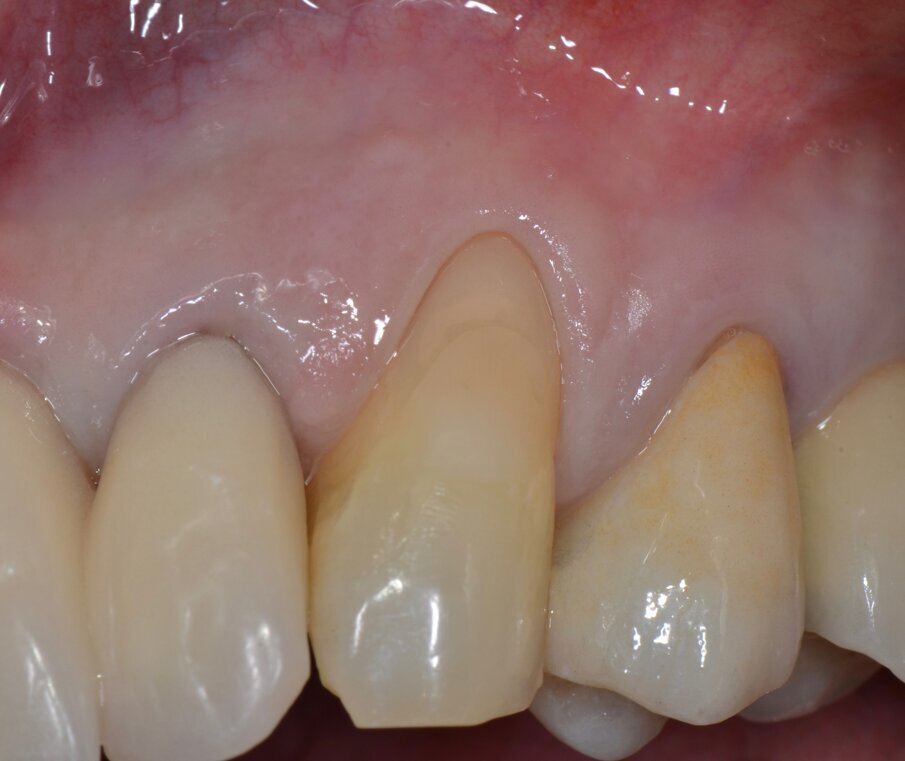

Riguardo al comparto intraorale, dalle radiografie diagnostiche e dall’esame parodontale e occlusale sono emersi aspetti che meritavano una correzione anche nei settori posteriori, ma la paziente ha deciso di effettuare inizialmente il trattamento dei soli gruppi frontali superiore e inferiore demandando a un momento successivo le problematiche dei quadranti posteriori (Figg. 2-6). Nel gruppo frontale superiore si possono notare recessioni gengivali sugli incisivi centrali, che sono anche molto ruotati, e sul canino di sinistra; corone in metallo-ceramica sugli incisivi laterali con esposizione del bordino metallico e una corona in ceramica metal-free sul canino di destra. Inoltre è molto evidente lo squilibrio delle parabole gengivali tra i due canini, per cui per ristabilire un’estetica ottimale sarà necessario anche interessare i tessuti molli eseguendo una chirurgia resettiva sul canino di destra e, al contrario, un lembo a posizionamento coronale sul canino di sinistra (Fig. 7).

Dopo circa un mese viene eseguito un lembo a scorrimento coronale con innesto di tessuto connettivo (CAF+CTG) prelevato dal palato con la “Tecnica di Langer e Langer mod. J.Bruno” per coprire la recessione sul canino superiore sinistro e ispessire il tessuto sopra il quale verrà posizionata una faccetta in ceramica (Figg. 12-17). A due mesi dal CAF+CTG si può notare la maturazione dell’innesto con un ottimale spessore mantenuto e lo spazio guadagnato sul canino controlaterale con la ORS (Figg. 18, 19).